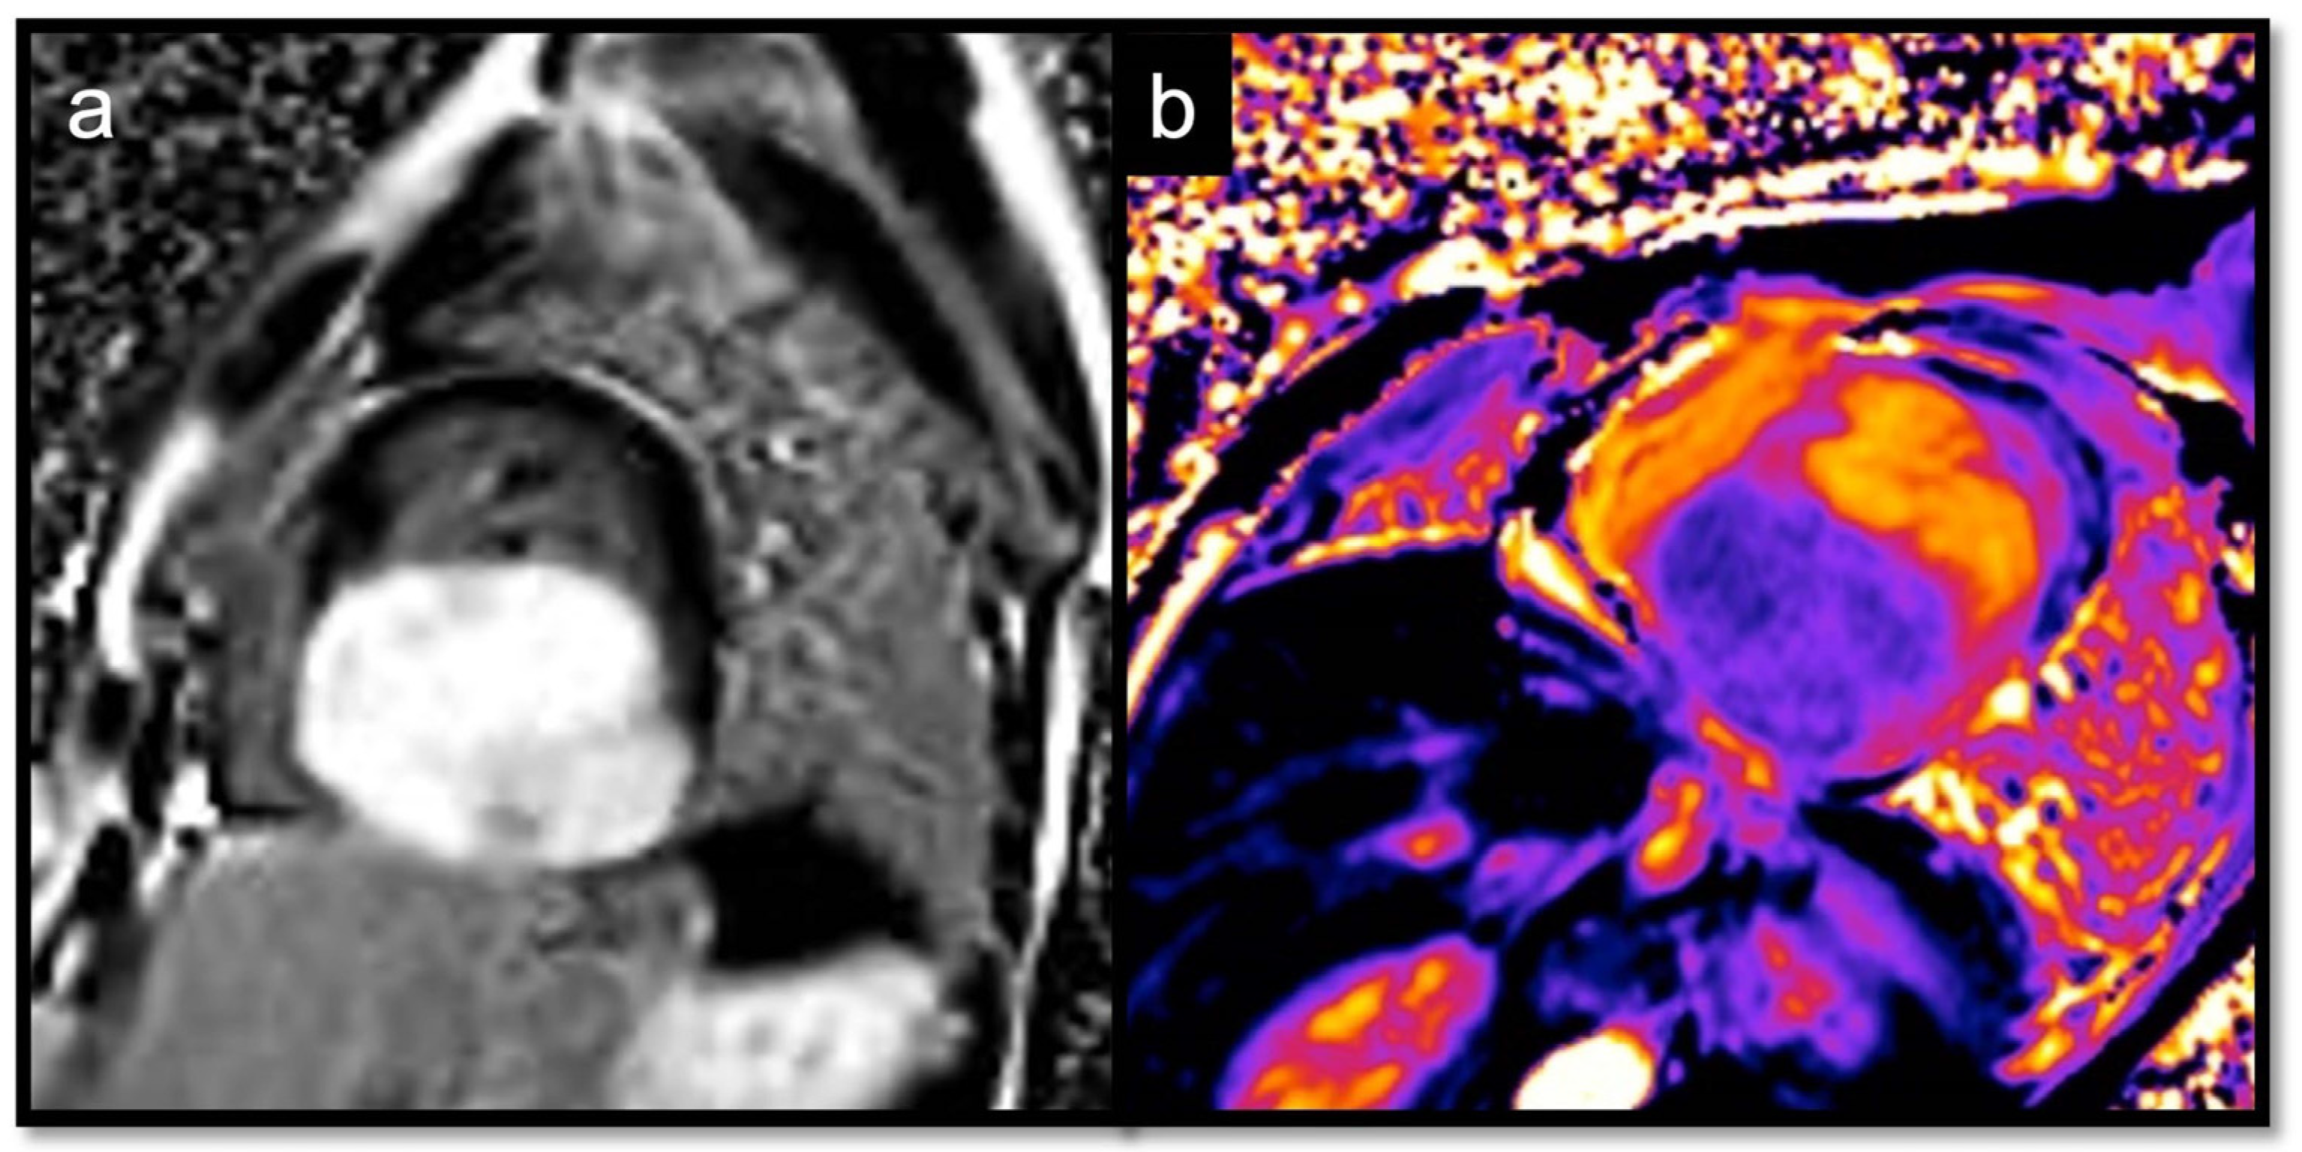

- Short T1/short T2 (as compared with the myocardium) for calcifications

- Short T1/long T2 for melanoma or lipomas and lipomatosis [64]

- Long T1/long T2 for most tumors, whether benign or malignant, with different degrees in particular for the T1 (close to the myocardium for rhabdomyoma, long or very long for myxomas [65] and fibroelastomas)

- T1 mapping allows for highlighting the difference between recent (<1 week) and old thrombi (>1 month), as recent thrombi have a significantly shorter T1.